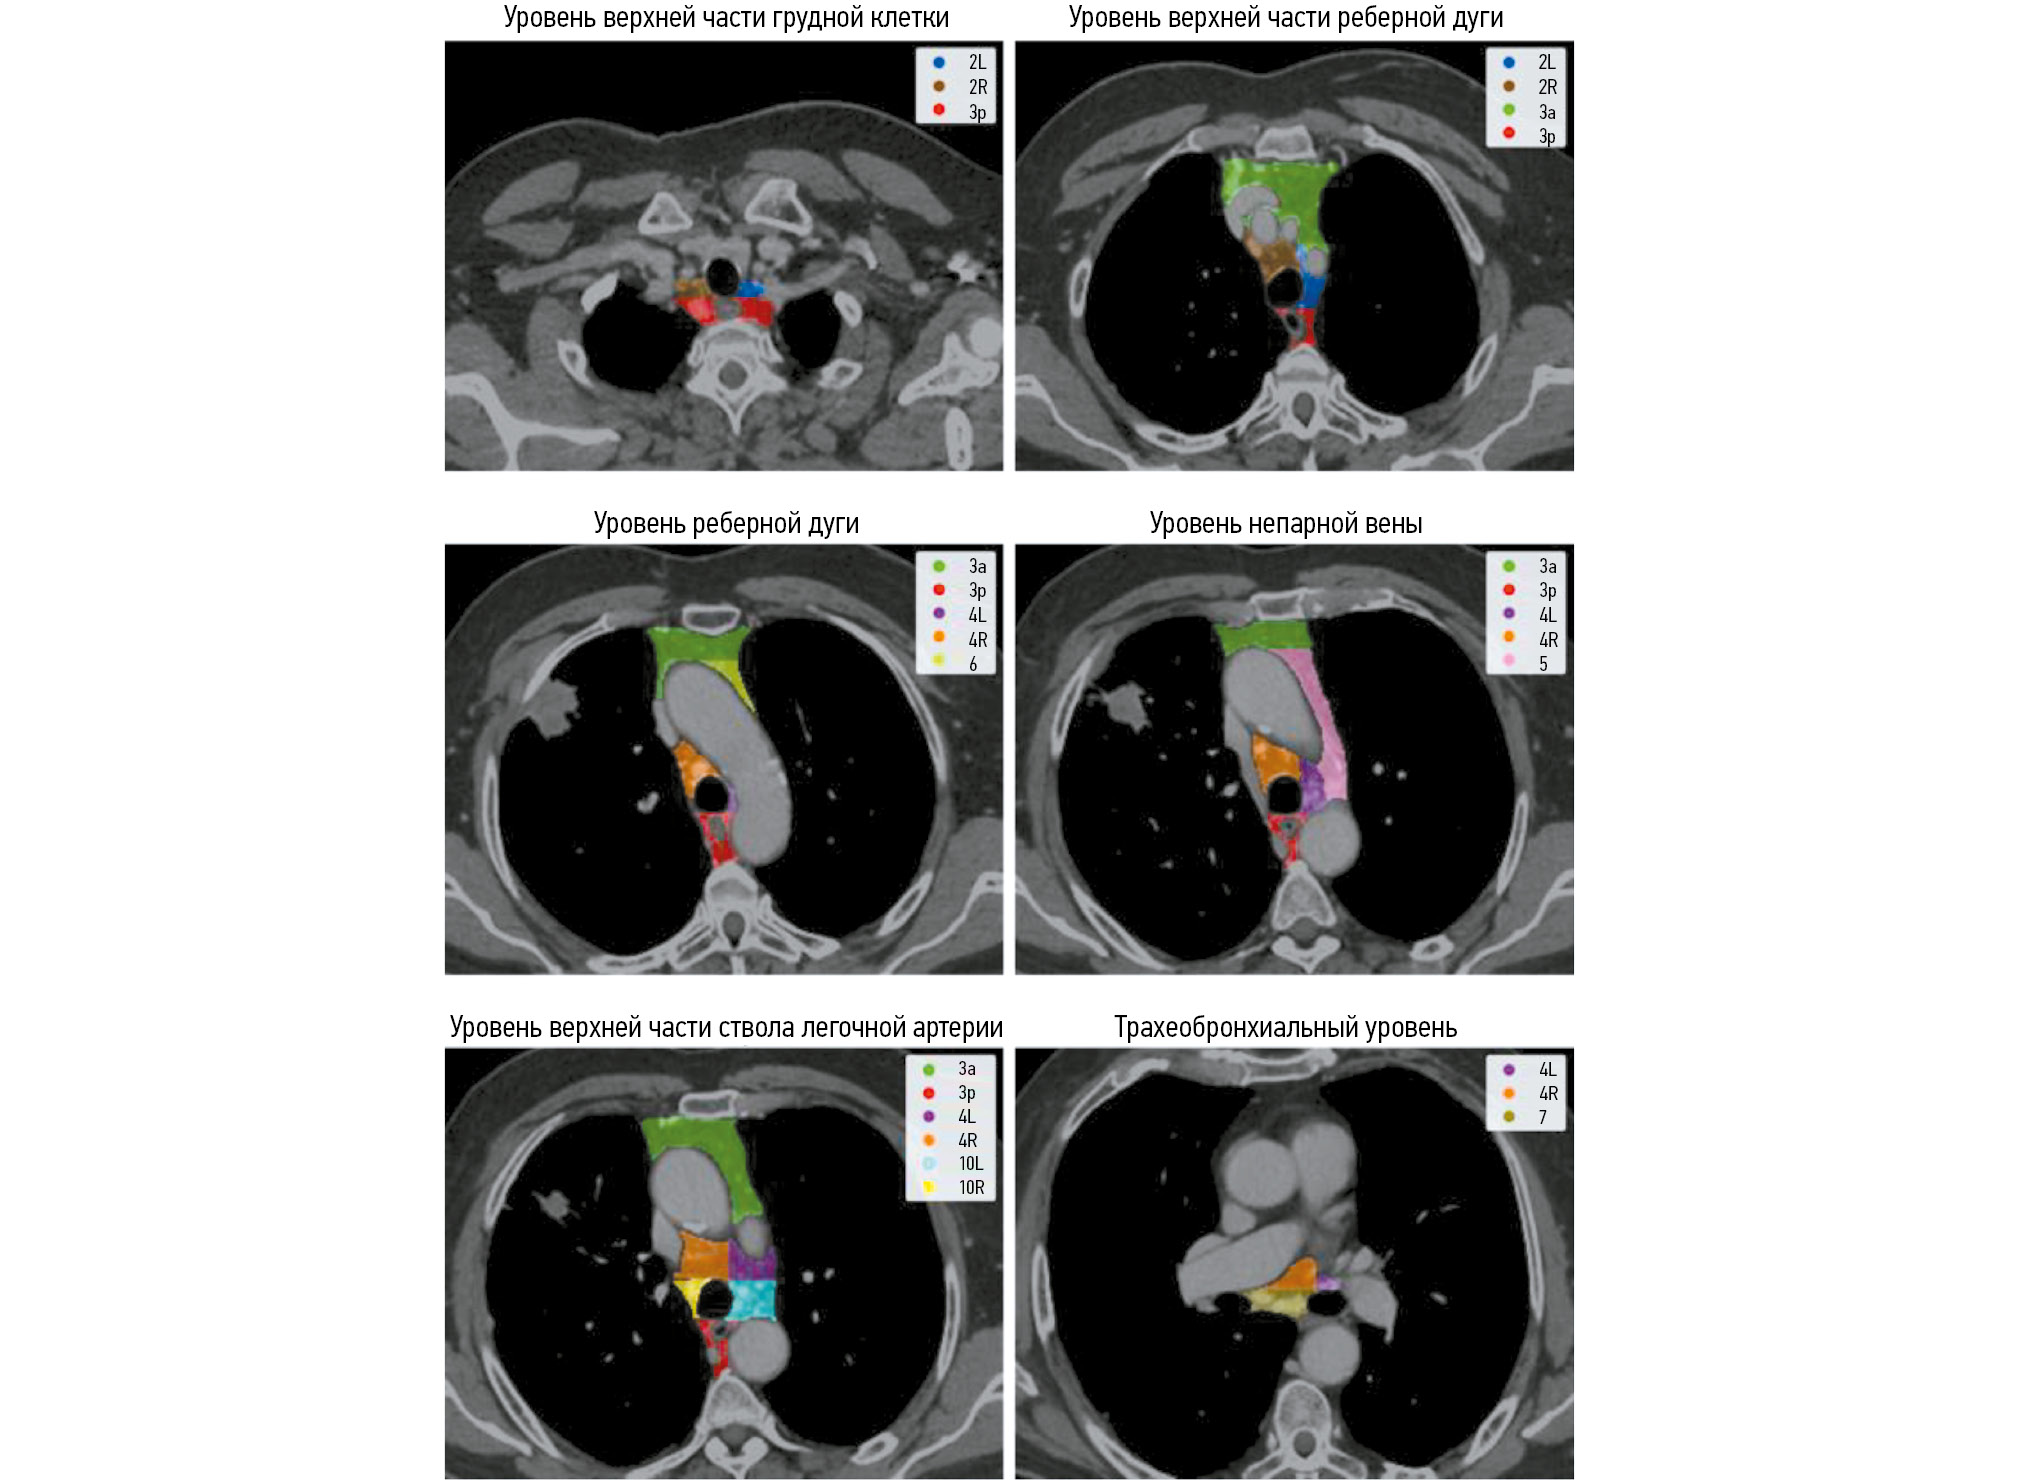

Segmentation of the lymph node groups

In patients with NSCLC, the affected lymph nodes are located in a narrow range (mediastinal area). The anatomical and primary tumor sites dictate the extent of regional lymph node involvement [12]. The International Association for the Study of Lung Cancer (IASLC) guidelines recognize ten lymph node groups in the mediastinum [40]. Lymph node groups near the trachea and bronchi are divided into left and right groups. No additional specialized classification system is used for the subcarinal lymph nodes. During diagnostic procedures, biopsies are not typically performed for Groups 1, 8, and 9 lymph nodes. Therefore, they were excluded from this study.

The same radiologist annotated the lymph node groups, meticulously adhering to the IASLC guidelines for generating prognostic maps for the mediastinum [40]. The annotation protocol required that large blood vessels, such as the aorta, pulmonary trunk, and azygos vein, as well as the esophagus, be differentiated from the lymph node groups (Fig. 2).

Fig. 2. Example of lymph node group annotation at different mediastinal levels.